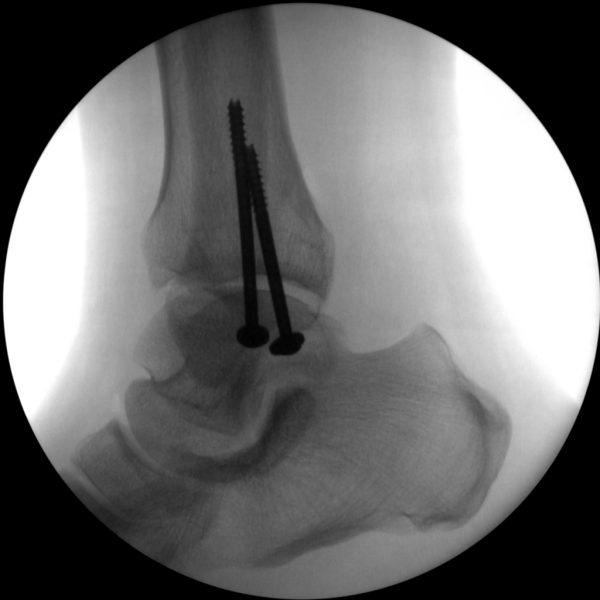

Hip fixation

Clinical Evidence

Skan-C is a great C-arm for orthopaedic treatments for several reasons